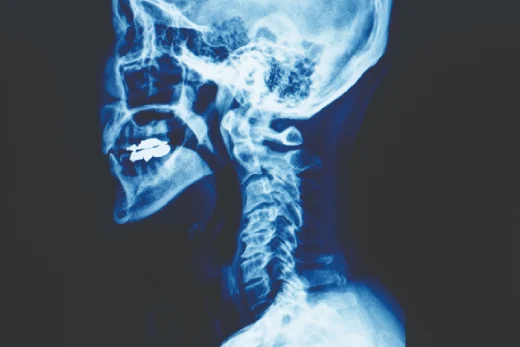

Spine surgery is a surgical field used for the treatment of diseases related to the spine. As a result of structural, mechanical, or functional problems in the spine, the person cannot move the spine comfortably and feels constant pain. Disc problems, joint calcification, or herniated discs can lead to impaired function of the spine. If a person is experiencing this type of pain, he/she should definitely go to the hospital immediately. There is, of course, a way to cure these problems in the spine, called spinal surgery.

There are some types of spine surgery;

These can be listed as discectomy and microdiscectomy, disc prosthesis, laminectomy, spinal fusion, corpectomy, and vertebroplasty.